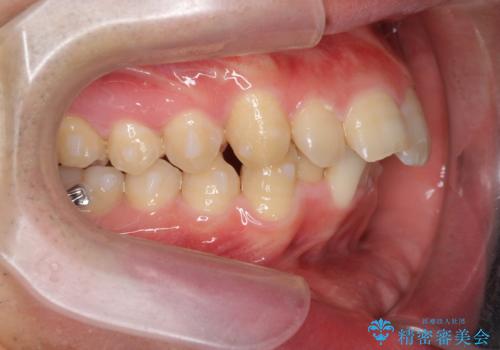

ガタつきの大きい前歯 インビザラインによるマウスピース矯正治療

- ガタつきの目立つ前歯の改善を求めて来院されました。

上顎前突、がたつきを改善すべく上顎臼歯の後方移動・ディスキングを行い歯並びの改善を計画します。

食事・歯ブラシ時以外の時間にしっかりとマウスピースを装着していただけたのでガタつきは大きく改善し良好な歯並びを得ることができました。